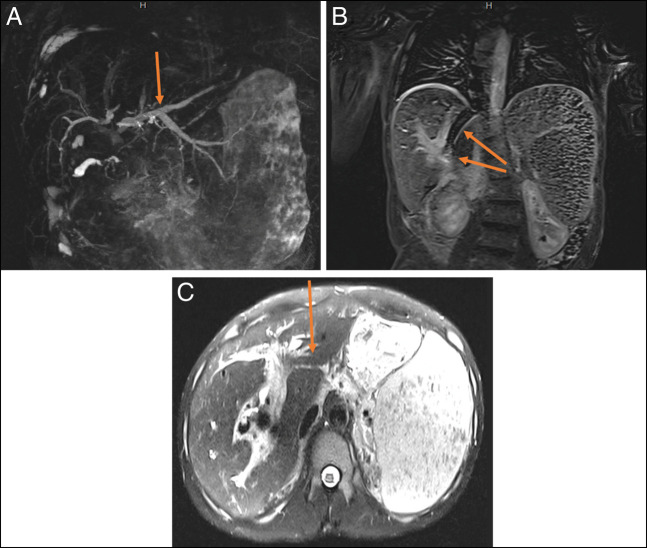

The patient was a 29-year-old man who initially presented to our center with concerns of generalized body aches and was found to have a column of air within his transjugular intrahepatic portosystemic shunt (TIPS) stent and a fistulous connection between his common bile duct (CBD) plastic stent and uncovered metal TIPS stent (Figure 1). He had a history of chronic portal venous thrombosis in the setting of a hypercoagulable state from systemic lupus erythematous with a positive lupus anticoagulant. This led to cavernous transformation resulting in portal biliopathy with complications of recurrent ascending cholangitis, bacteremia, and abscess formation. This was managed with multiple CBD stents and eventually a TIPS procedure with an uncovered stent at an outside center.

For unclear reasons, the plastic CBD stent was not replaced for over a year and the patient had declined prior surgical interventions such as a mesocaval shunt. When he presented to our center, the patient had abdominal pain that was worked up by CT, which showed a column of air within a TIPS stent that was occluded at both the proximal and distal ends with concern for a fistula between the CBD stent and the TIPS stent. The gastroenterology team further evaluated this by endoscopic retrograde cholangiopancreatography (Figure 2), during which time, the CBD stent was removed; a fistulous connection between the prior CBD stent and the uncovered TIPS stent was confirmed; and a covered metal stent was placed in the CBD. The patient also had a new Citrobacter braakii bacteremia during this hospitalization, which further confirmed that the GI enteric flora was able to enter the systemic circulation through the fistulous connection. Further intervention by interventional radiology was impeded by concern that the column of air within the TIPS stent would lead to an air embolus during any procedure. The patient was further evaluated by general surgery and vascular surgery; however, further definitive treatment was deferred in the setting of severe thrombocytopenia secondary to immune-mediated thrombocytopenia. His immune-mediated thrombocytopenia was managed with medical therapy initially but was refractory requiring splenectomy with initial improvement, although later it relapsed. He was discharged with close follow-up with planned outpatient CBD stent exchange.